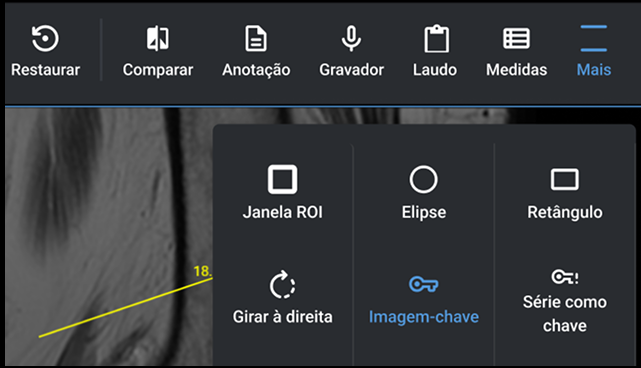

Cree informes mediante reconocimiento de voz, dictado digital y plantillas de informes estándar con solo unos pocos clics. Agregue imágenes y vídeos clave para informes multimedia.

Acceda a imágenes, informes y archivos adjuntos en su teléfono inteligente. Notificar a los pacientes y solicitantes cuando haya un resultado disponible. Inicie sesión a través del CÓDIGO QR para que los pacientes y

solicitantes puedan acceder a los resultados fácilmente.

Acceda a imágenes, informes y archivos adjuntos en su teléfono inteligente. Notificar a los pacientes y solicitantes cuando haya un resultado disponible. Consulte sus resultados desde 1 solo link.